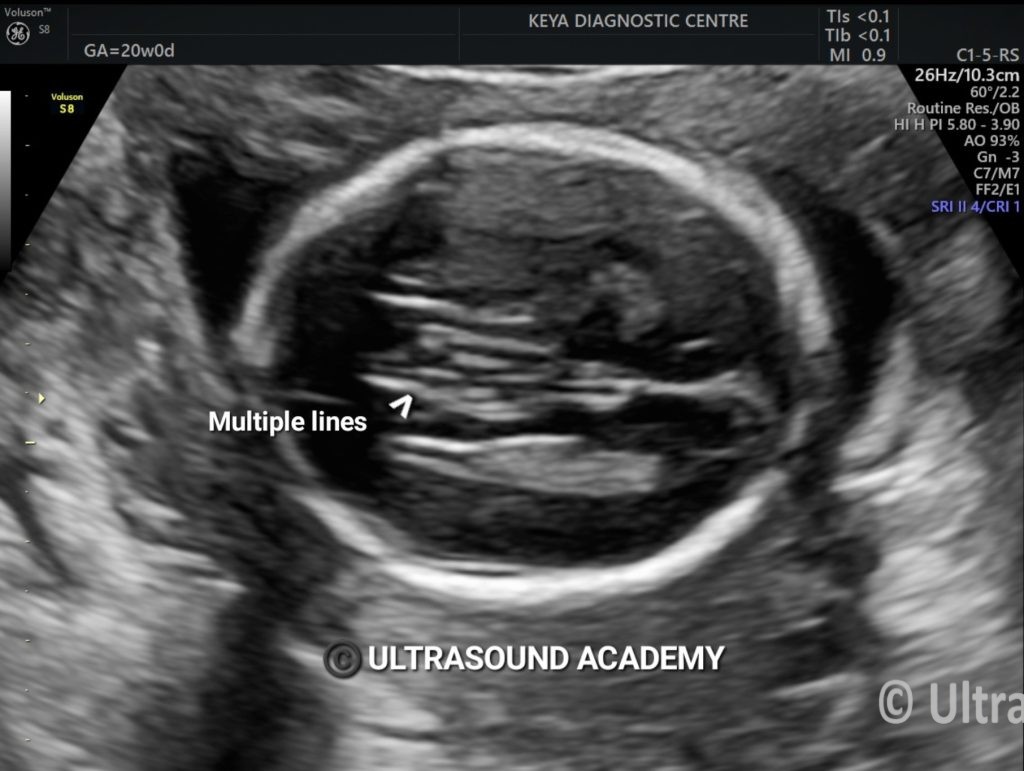

CORPUS CALLOSUM AGENESIS

Findings : Absence of corpus callosum. Frontal horns appears widely separated, Absence of CSP.

Ultrasound findings on ultrasound :

·         lateral ventricles

o    widely spaced parallel bodies (racing car sign)

o    small frontal horns

o    colpocephaly: which can give a “teardrop” configuration on axial scans

·         septum pellucidum: absent

·         interhemispheric fissures: widened